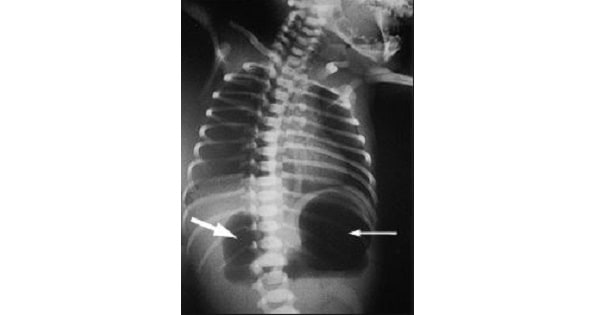

Question A newborn had a bilious vomiting after 6 hours of birth. X-ray of the abdomen shows as represented in the picture below. This is a feature of ? A. Pyloric stenosis. B. Duodenal atresia. C. Ileal atresia. D. Esophageal atresia. Show Answer Correct Answer » B Explanation Ans:B. Duodenal atresia “Double bubble” sign […]